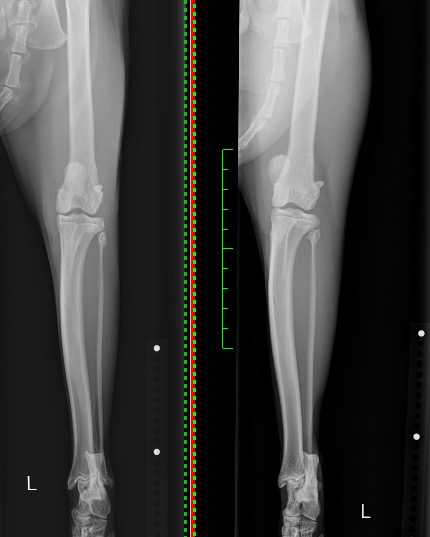

術前(右)・術後(左)のX線写真を比べると、術後では膝蓋骨がしっかりと大腿骨の真ん中に位置し、脱臼が整復されているのがお分かりいただけるかと思います。